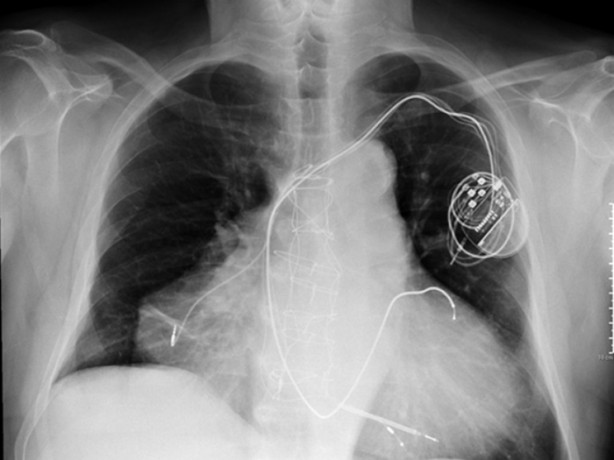

İki kalbi olan adam - Verona, Italya'da yaşayan kalp krizi geçiren adamın doktoru tarafından görüntülenen iki kalbi